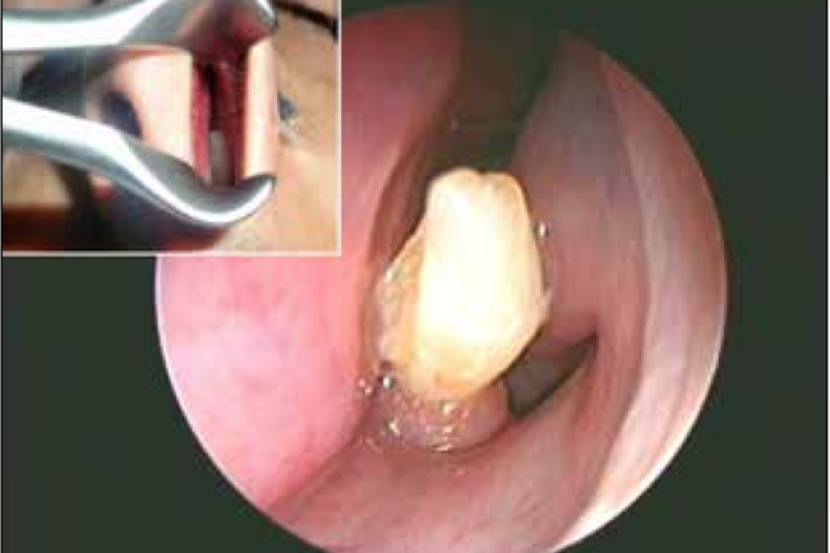

Mana tidaknya, apabila pemeriksaan dilakukan terhadap hidung lelaki berusia 22 tahun itu, doktor menemui sebatang gigi yang tumbuh dengan sempurna.

Bagaimanapun hasil usaha kumpulan doktor pakar, gigi berkenaan berjaya dicabut bagi memberikan keselesaan kepada pemuda terbabit.